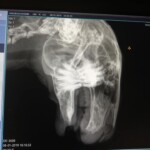

Otík je jako mnoho králíčků, kteří se k nám dostali nalezenec. Našel se v šíleném stavu. Měl ohromně přerostlé zuby. Horní řezáky asi 5 cm přerůstaly z tlamy a spodní tvořily jakési spirály zabodávajíví se do horního pysku. Řezáky mu bohužel byli na předchozím nespecializovaném pracovišti uštípnuty kleštěmi. V místě kde se zuby zařezávaly do pysku vznikla kapsa plná hnisu. Ta mu byla vypláchnuta dezinfekcí. Řezáky i stoličky byly sbroušeny v inhalační narkóze. Otík má pravděpodobně způsobenou nějakým úrazem nefyziologicky postavenou čelist (zda se jedná o špatně srostlou frakturu budeme zjišťovat při další návštěvě). O jeho pravé oko přišel pravděpodobně infekcí a nebo taky úrazem. Poškozené oko prasklo a atrofovalo. Jelikož oko dělá neplechu a hnisá bude muset být vyndáno. To však momentálně v Otíkovu zdravotním stavu není možné. V jeho krásných dlouhých uších má ošklivý zánět. Byl znečištěný zaschlými výkaly jelikož má průjem. I když to tak na fotkách nevypadá je úplně kachektický. Takto velký králík by měl vážit tak 4 kg a ne 1,5 kg jako váží Otík. Ano, pouhých 1,5 kg totálně zuboženého tvora. A v neposlední řadě má Otík parazity v kožíšku. Momentálně je Otík na lécích. Budeme čistit uši, kapat oko a hlavně pořádně dokrmovat/vykrmovat protože je potřeba, aby pořádně nabral. V takovéhle stavu by enukleaci oka a extrakci řezáků nepřežil.

14.11.2018 – Podstoupil Otík operaci – enukleaci pravého očního bulbu a broušení zubů v inhalační narkóze

Otík podstoupil další operaci – extrakci řezáků a broušení stoliček. Čištění zvukovodů a odběr vzorků na kultivaci.